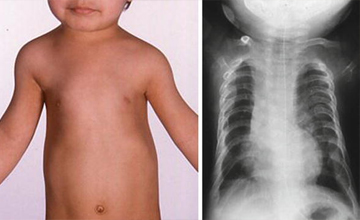

Pektus Karinatum

Pektus Karinatum (Güvercin Göğsü)

Pektus ekskavatum sternum ve kıkırdak kostaların değişik derecelerde depresyonu ile karakterize ...